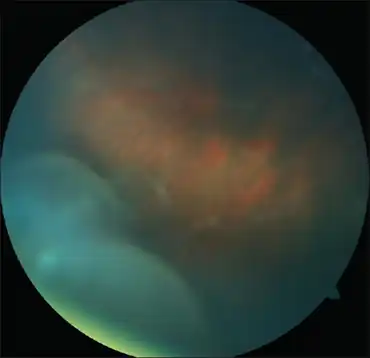

| Anterior vitreous cells in Intermediate uveitis | |

Intermediate uveitis is a form of uveitis localized to the vitreous and peripheral retina. Primary sites of inflammation include the vitreous of which other such entities as pars planitis, posterior cyclitis, and hyalitis are encompassed. Intermediate uveitis may either be an isolated eye disease or associated with the development of a systemic disease such as multiple sclerosis or sarcoidosis. As such, intermediate uveitis may be the first expression of a systemic condition. Infectious causes of intermediate uveitis include Epstein-Barr virus infection, Lyme disease, HTLV-1 virus infection, cat scratch disease, and hepatitis C.